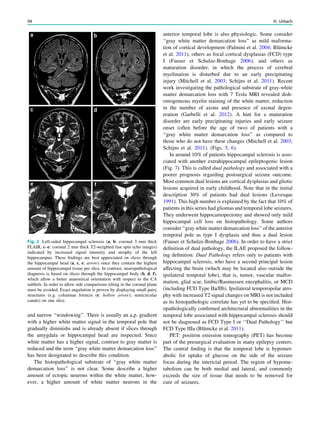

Fig. 2 Epileptogenic lesion and symptomatogenic zone. A 40-year-

old woman suffered from complex focal seizures with a fearful face

and body rocking. The symptoms thus pointed to the mesial frontal

lobe as the origin. MRI shows right-sided hippocampal sclerosis

(a, arrow). Simultaneous video and EEG recordings from interhemi-

spheric (c) and convexity strip and intrahippocampal depth (b) elec-

trodes show seizures starting in the right hippocampus (d, arrow).

Clinical symptoms start around 1 s afterwards (d, asterisk)

22 H. Urbach

seizure onset zone which it is intended to be removed, and

this is defined as the brain area in which ictal EEG activity

starts. The epileptogenic lesion usually shows at least some

overlap with the seizure onset zone and is therefore a good

indicator for its localization (Fig. 1).

Other frequently used terms are irritative area, defined as

the brain area with interictal EEG activity, eloquent cortex,

defined as the cortex area with important functions such as

language, motor, and visual field functions, and symptoma-

togenic area, defined as the brain area in which epilep-

togenic activity leads to clinical symptoms. If epileptogenic

activity spreads rapidly, the epileptogenic lesion and the

symptomatogenic area can be far from each other (Fig. 2).